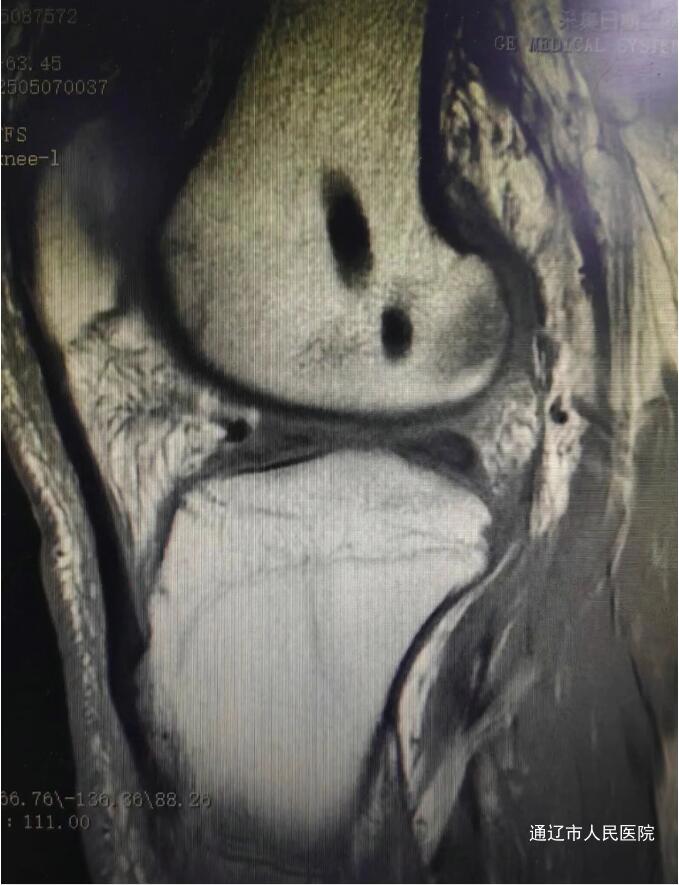

术前

(前交叉韧带损伤MRI图像)